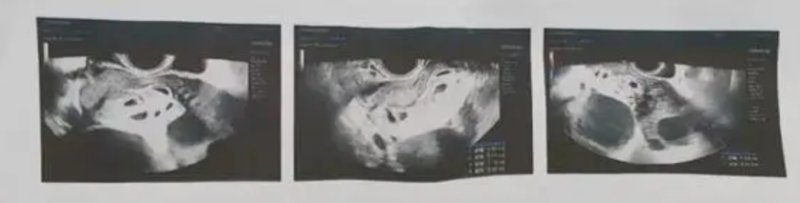

28일(현지 시각) 사우스차이나모닝포스트(SCMP)에 따르면 중국 장시성 난창에 거주하는 25세 여성 후씨는 지난해 아홉 쌍둥이를 임신한 사실로 큰 화제를 모았다.

사실 그는 임신에 계속 어려움을 겪던 중 배란촉진제를 주사해 임신에 성공한 것이었으며, 의료진은 다태아 임신의 위험성을 고려해 7명의 태아를 유산시키는 수술을 권유했다.

후씨는 지난해 11월 해당 수술을 받은 뒤 남은 2명의 태아는 건강하게 자라고 있다는 소식을 전했었다.